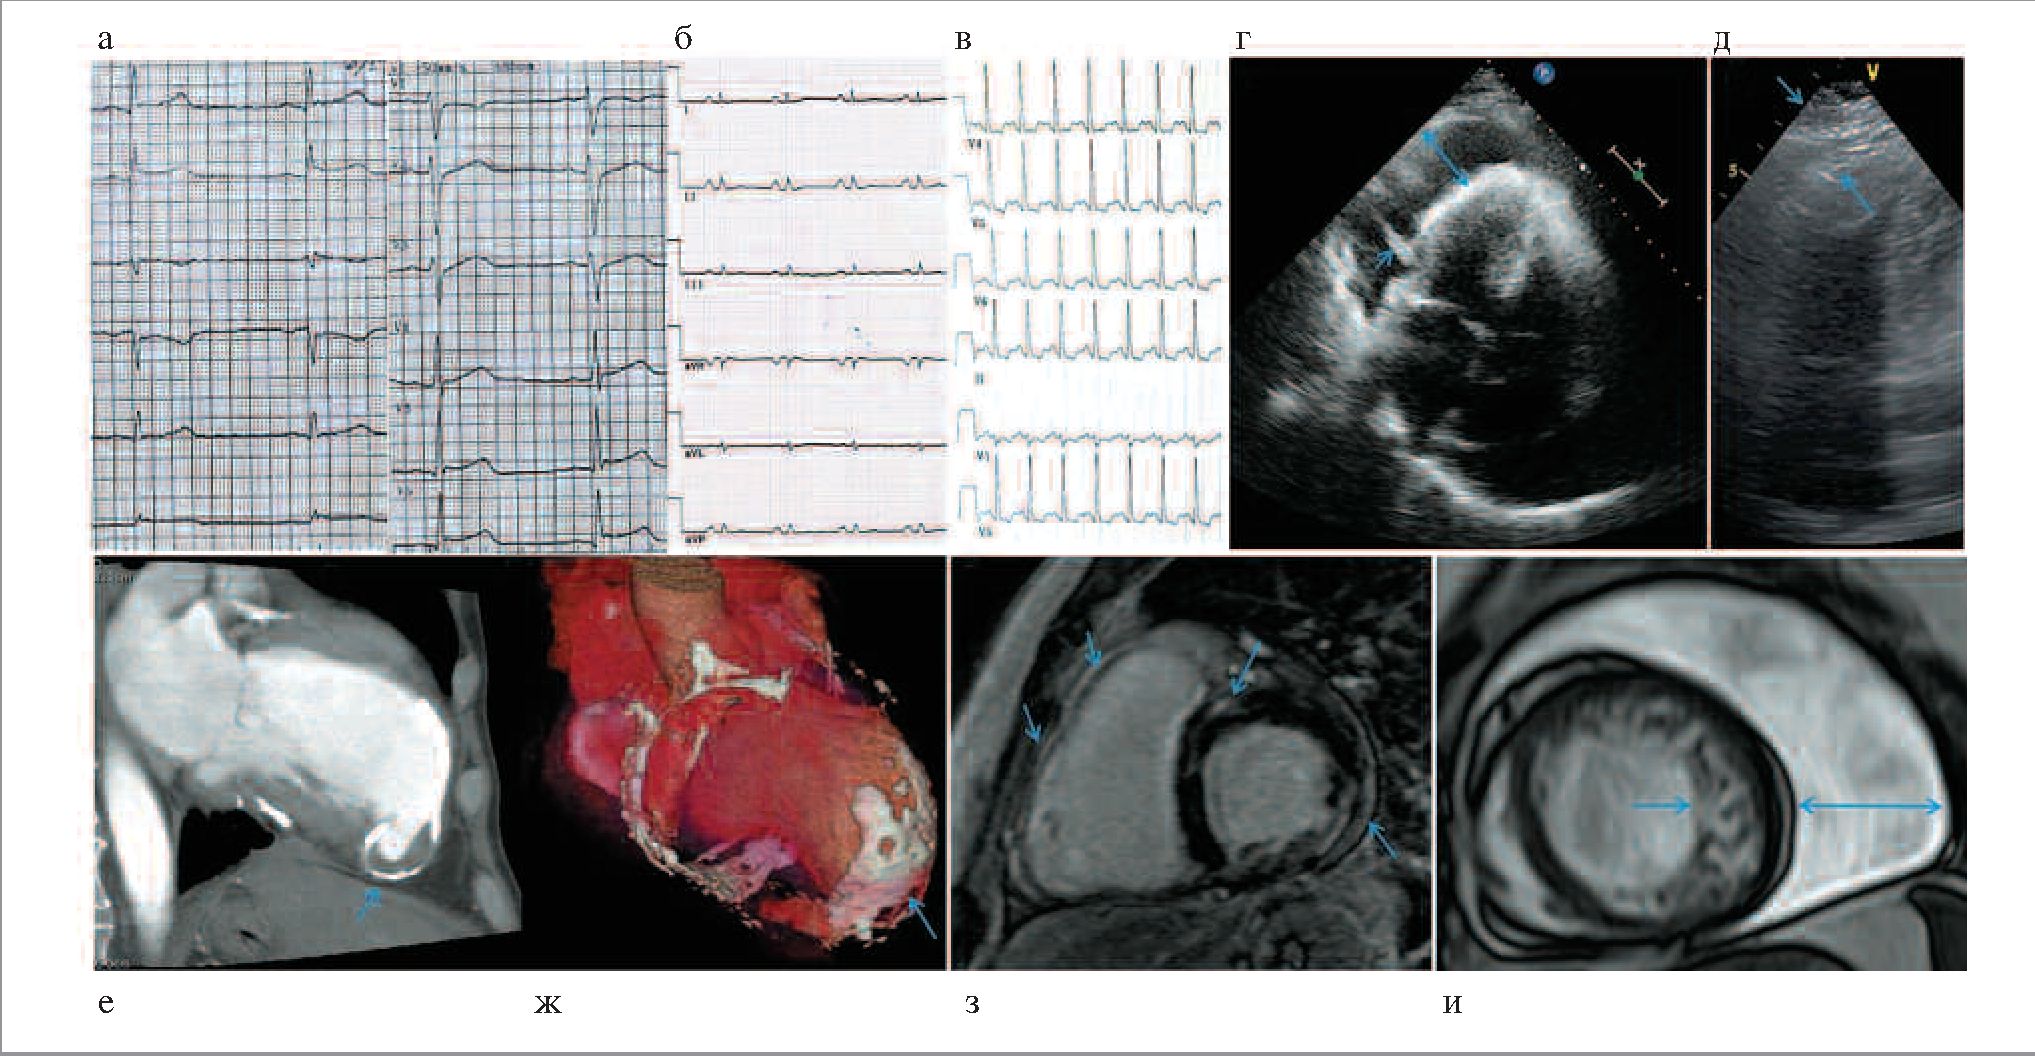

Повышенный уровень тропонина (у единственного больного с острым вирусным перикардитом) подтверждал одновременное развитие острого миокардита. Уровень предсердного натрийуретического фактора (BNP) в полной мере не отражал симптомов (боль, тяжесть в груди, одышка), хотя у пациентов с выраженной одышкой вследствие перикардита, как правило, он повышен. Изменения на ЭКГ включали снижение вольтажа комплексов QRS (n=12, 16%; рис. 2, б, см. на цветной вклейке), подъем сегмента ST (n=5, 7%; рис. 2, а), а также малоспецифичные изменения зубцов Т (n=29, 38%), патологические зубцы Q/комплексы QS (n=4, 5%), признаки гипертрофии левого желудочка – ЛЖ (n=14, 18%), блокаду передней ветви левой ножки пучка Гиса (n=13, 17%), полную блокаду левой и правой ножек пучка Гиса (по 1 больному, 1%) и неполную блокаду правой ножки (n=5, 7%).

Рис. 2. Неинвазивная инструментальная диагностика при перикардитах различной этиологии: а - ЭКГ больного с острым вирусным миоперикардитом (скорость записи 50 мм/с): диффузный подъем сегмента ST (отведения II, III, aVF, V3-V6); б - ЭКГ больного с констриктивным перикардитом (скорость записи 25 мм/с): снижение вольтажа комплекса QRS, признаки гипертрофии предсердий; в - ЭКГ больного 28 лет с лейкокластическим васкулитом, тредмил-тест (скорость записи 25 мм/с): частота сердечных сокращений 140 уд/мин, ишемическая депрессия сегмента ST; г - ЭхоКГ при подостром туберкулезном перикардите с большим выпотом (стрелки: размер выпота и нити фибрина в полости перикарда); д - ЭхоКГ при констриктивном туберкулезном перикардите (стрелки - резко утолщенные, спаянные листки перикарда); е, ж - МСКТ больного с ложной аневризмой АЖ (стрелки) и констриктивным кальцинированным перикардитом в исходе синдрома Дресслера; з - МРТ больного с миоперикардитом (стрелки - отсроченное контрастирование гадолиния) и аритмогенной дисплазией правого желудочка; и - МРТ больной с некомпактным миокардом АЖ (левая стрелка) и массивным выпотом в перикарде (правая стрелка) после лучевой/химиотерапии по поводу лимфогранулематоза.

Туберкулезный перикардит диагностирован у 10 (14,1%) больных, средний возраст 58,0±15,1 (от 31 до 79) года, у 1 − в сочетании с ГКМП. Вирус-позитивных пациентов нет. В 60% случаев выпот >10 мм и в 50% – от 20 мм и более; в 70% выявлен фибрин (рис. 2, г), в 50% – признаки констрикции (что сопровождалось уменьшением объема выпота или его исчезновением; рис. 2, д). В одном случае медленное накопление большого количества жидкости приводило к развитию тампонады (неоднократно выполнялись пункции). Значительное утолщение листков перикарда по данным ЭхоКГ и МСКТ отмечено в 70%. Паратуберкулезный миокардит диагностирован у 1 больной.

К этой группе нами отнесены также больные AL-амилоидозом и скелетной миопатией (экссудативно-констриктивный перикардит, который усугубил ХСН в рамках амилоидной кардиомиопатии), тромботической микроангиопатией (вероятно, вторичной) у пожилого больного полисерозитом и с тяжелой ХСН вследствие ишемии миокарда с некрозом, а также с ANCA-позитивным панкардитом Леффлера (перикардит с локальными спайками привел к скоплению жидкости за верхушкой правого желудочка и его существенной деформации, что стало одним из показаний к операции; рис. 3, б, в). Лейкокластический васкулит у ANCA-негативного больного диагностирован при биопсии перикарда (рис. 3, г, д), о миокардиальном васкулите говорили стенокардия и ишемическая депрессия сегмента ST на ЭКГ (рис. 2, в).

Перикардит, ассоциированный с ИБС, диагностирован у 3 (4%) больных, средний возраст 66,0±6,2, срок наблюдения 22 (18; 60) мес. Во всех случаях проводились вмешательства по поводу ИБС (в том числе коронарное шунтирование, стентирование), однако в 1 случае повторные пункции (по поводу синдрома Дресслера) с нагноением в анамнезе лишь способствовали развитию псевдоаневризмы ЛЖ с кальцификацией перикарда (рис. 2, е, ж) и еще в одном выпот «случайно» выявлен одновременно с инфарктом и поддается стероидам с переходом на колхицин.

В последнем случае выпот достигал 700−800 мл, назначение диуретиков и стероидов, а также попытки получить жидкость успеха не имели; несмотря на одновременное выявление некомпактного миокарда (рис. 2, и) и значимую систолическую дисфункцию (ФВ 22%), выполнена субтотальная перикардэктомия с субъективным улучшением и возрастанием ФВ до 35%; данных по поводу хилоперикарда не получено, экссудат серозно-геморрагический, при морфологическом исследовании отмечен выраженный фиброз перикарда с остаточными признаками воспаления (рис. 3, е, ж). У остальных пациентов объем выпота средний и малый, фибрин не определялся, плевральный пунктат у двоих неспецифичен. Диагноз опухоли поставлен с помощью КТ/МРТ органов грудной клетки, заподозрен при ЭхоКГ. Больная с саркомой перикарда погибла через 1 мес после попытки оперативного лечения.